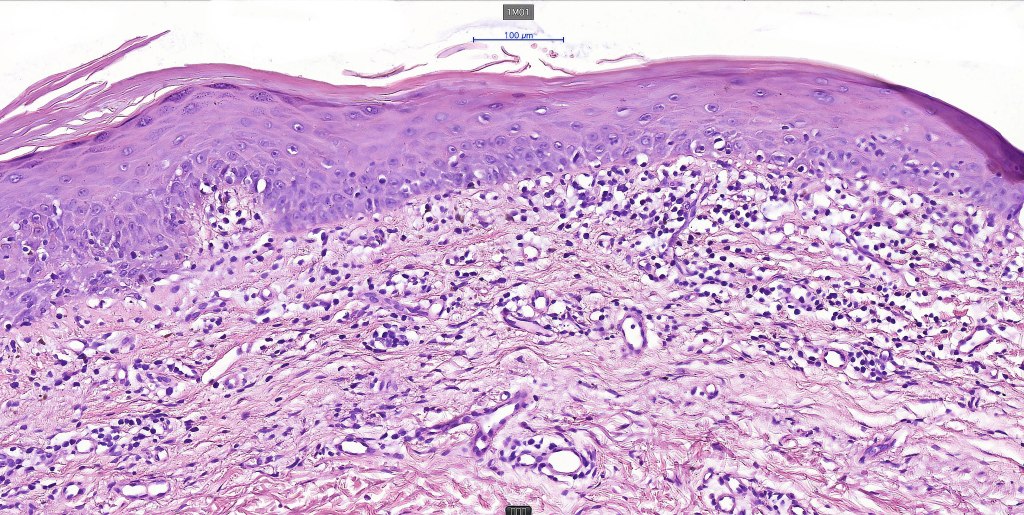

Histological features

The histological hallmark of mycosis fungoides is the presence of large atypical lymphocytes with a convoluted/cerebriform nuclear border (Sézary cells). These may be found at the epidermal-dermal jnuction and as collections within the epidermis (Pautrier microabscess). These are most easily found in plaque stage disease. The epidermal component can be subtle in patch stage disease and is often lost in tumor stage dsease. The classification into patch, plaque & tumor stage disease is less helpful histologically as the features merge from one to the other. It is all a matter of degree.

Patch stage disease

•Changes can be subtle & dependent on clinicopathological correlation; in many patients sequential biopsies over many months may be necessary to establish the diagnosis.

•Mild hyperkeratosis & focal parakeratosis, acanthosis, epidermal atrophy or of normal thickness

•Superficial dermal lymphocytic infiltrate containing variable numbers of Sézary cells with atypical, irregular, hyperchromatic nuclei surrounded by a halo; these can be very few in number and dependant on viewing multiple levels

•Palisading of atypical lymphocytes along the epidermal-dermal border

•Pautrier microabscesses may be present but are often absent in patch stage disease

•Variable interface change with keratinocyte necrosis & pigmentary incontinence

•Eosinophils & plasma cells sometimes present

•Coarse collagen bundles in the papillary dermis can be a feature but this is not as marked as seen in plaque disease

.Although in typical mycosis fungoides fungoides, spongiosis is absent, exceptionally it can be a feature